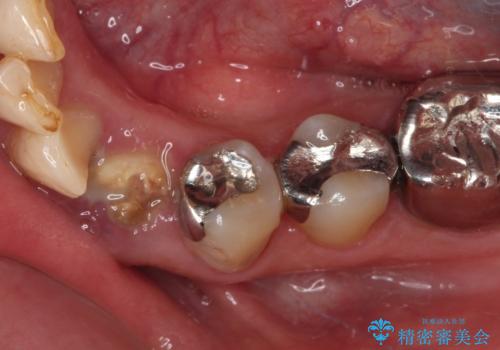

- クラウンがもげてしまった歯が抜歯と言われたとのことで来院された患者様です。

根管治療がされた歯であり、唇側に転位していたため、力がかかったことでクラウンが外れてしまったと判断されました。

麻酔下で歯肉を開いて診察をしたところ、唇側の歯肉縁下に深く歯が欠けている状態でした。